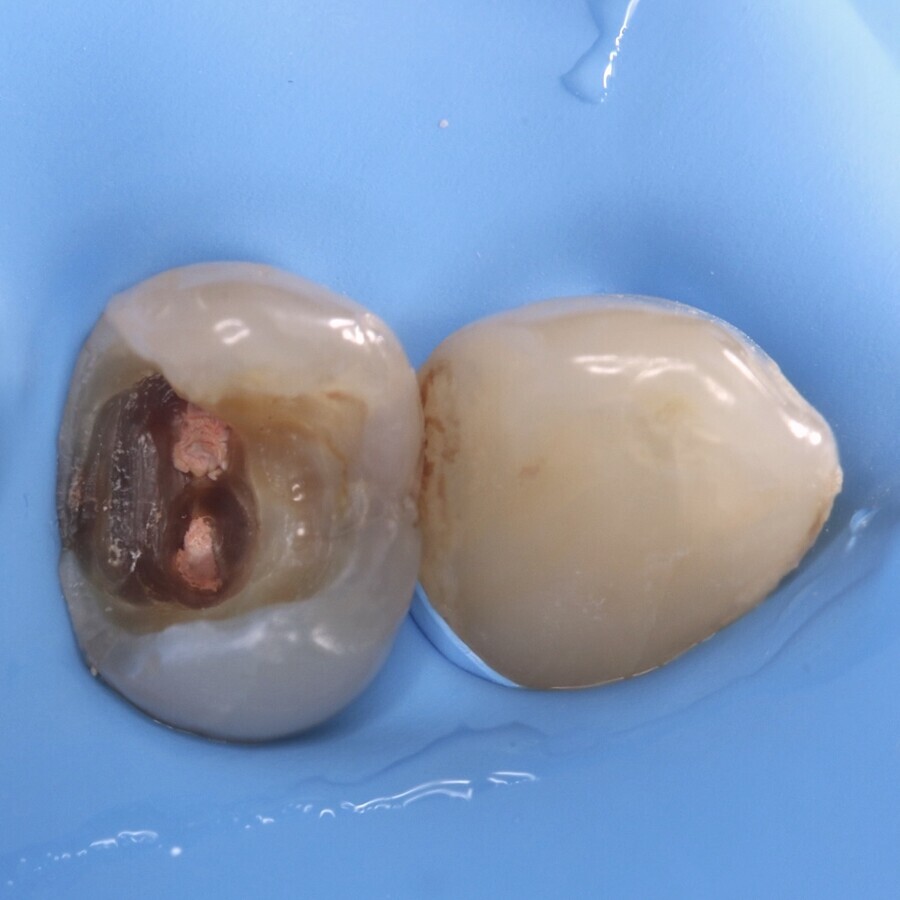

Antes de proceder con la limpieza de la cavidad, se toma una impresión de la anatomía con un material de barrera gingival (Gingival Barrier, SDI Ltd.) fijado en un micro-aplicador (Fig. 4), de forma que se pueda copiar la anatomía existente mediante la técnica del estampado oclusal (Fig. 5). Tras realizar la apertura de la cavidad (Fig. 6) se inicia la remoción selectiva del tejido cariado con una estrategia químico-mecánica (Fig. 7) hasta llegar a DENTINA FIRME en la base y dura en la periferia de la cavidad (Fig. 8) bajo aislamiento relativo utilizando Optragate (Ivoclar Vivadent) y rollos de algodón, se procede a aplicar el material restaurador EQUIA Forte fil (Fig. 9).

Fig. 7. Remoción selectiva del tejido cariado con una estrategia químico-mecánica hasta llegar a dentina firme.

Fig. 8. Acceso a dentina firme en la base y dura en la periferia de la cavidad bajo aislamiento relativo utilizando Optragate y rollos de algodón.

Fig. 9. Se procede a aplicar el material restaurador EQUIA Forte fil.